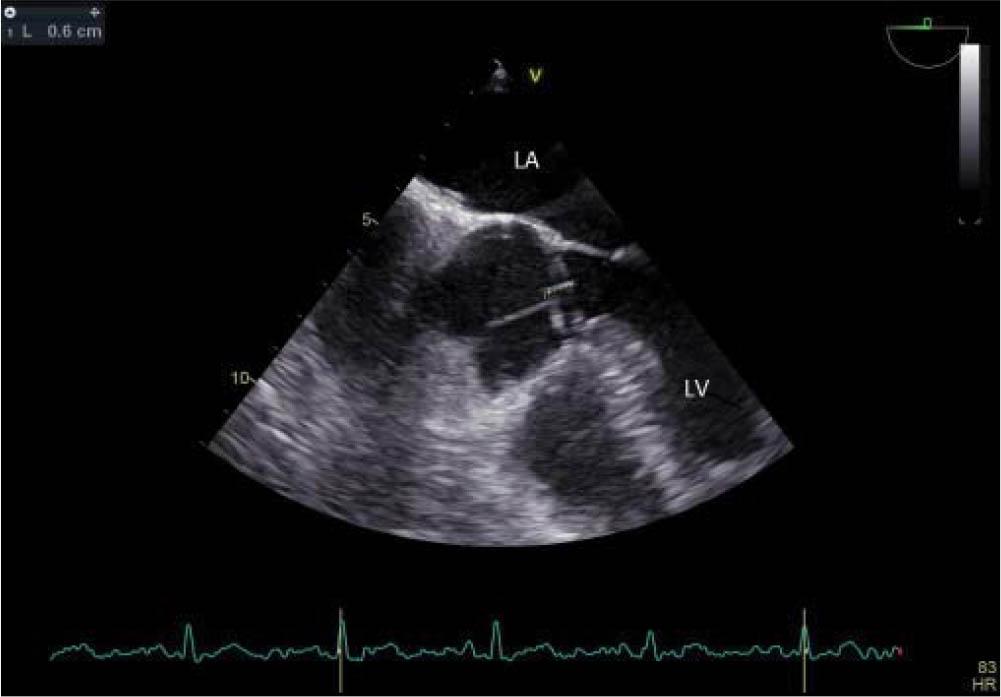

After four weeks of antibiotic therapy, in consideration of a possible surgical intervention, a second TEE was performed, which revealed no vegetation attached on the mitral valve and a much smaller aortic vegetation (6 mm diameter), attached to the NCC (Figure 7), NCC discontinuity with colour flow - high probability of perforation (without significant aortic regurgitation) and normal LV size and function. Heart failure biomarkers (NT-pro-BNP) were within normal limits (32 pg/mL), and the blood cultures (three sets) were negative at 37 days upon starting the antibiotic therapy.

Figure 7

Transesophageal echocardiography midesophageal 5 chamber view -a significantly reduced aortic vegetation (6 mm). LA left atrium, RA right atrium, LVOT left ventricle outflow tract, RVOT right ventricle outflow tract, LV left ventricle, Ao ascending aorta.